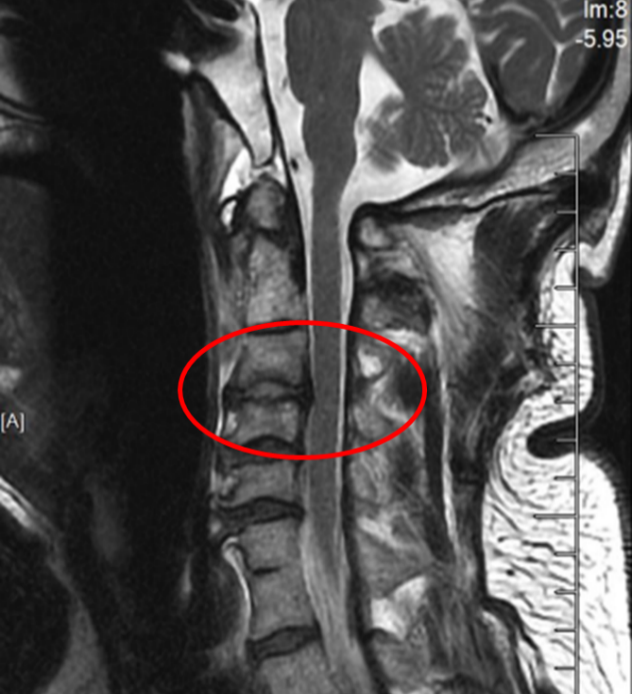

图3:骨科机器人

在麻醉手术科的严密监护下,刘义杰副主任医师首先熟练地完成了颈椎前路C3-4减压融合术(ACDF),成功解除了脊髓的压迫。然而,通过同一个仅3厘米的微小切口,精准地将螺钉植入游离且向后倾倒的齿状突具有极大的挑战性。关键时刻,骨科手术机器人发挥了“超级助手”的作用。团队利用机器人导航系统,对进钉点和角度进行了反复测算与调整,导针精准抵达目标。随后,由姜为民主任专利研发的一枚新型齿状突螺钉顺着通道顺利旋入,牢牢锁住了骨折端。整个过程出血量少,手术顺利完成。

此次手术的成功凝聚了苏大附四院脊柱外科团队多年来在上颈椎领域的深耕细作,是“微创理念”与“智能科技”完美融合的典范。特别是姜为民主任专利研发的新型齿状突螺钉,通过小切口实现了传统开放手术难以企及的精准与安全,兼具微创与稳固的双重优势,为此类疾患治疗带来更佳的方案选择。